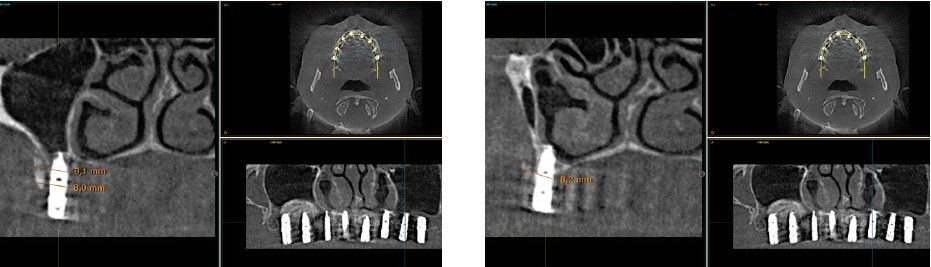

Fueron reclutados pacientes de forma retrospectiva con atrofia ósea horizontal severa (con anchura residual de cresta menor o igual a 3 mm), donde se colocasen injertos en bloque para regeneración ósea y posteriormente se insertarán implantes, con un tiempo de seguimiento tras la carga mayor o igual a 10 años. Antes de la colocación de los implantes, todos los pacientes fueron sometidos a una evaluación integral que incluyó modelos diagnósticos, un examen clínico intraoral detallado y un estudio tomográfico mediante Cone beam (TAC dental). Las imágenes obtenidas fueron analizadas con un software especializado (BTI-Scan III) para garantizar una planificación tridimensional precisa. Posteriormente, se llevó a cabo un encerado diagnóstico que sirvió como base para la creación de una guía quirúrgica, optimizando la ejecución de la rehabilitación planificada. La posición final de los dientes obtenida del encerado será la que guíe el proceso de regeneración para lograr el volumen óseo necesario para colocar los implantes en la posición necesaria. Antes de la inserción de los implantes se utilizó una pre-medicación antibiótica consistente en amoxicilina 2gr vía oral una hora antes de la intervención y paracetamol 1 gramo vía oral (como analgésico). Posteriormente los pacientes prosiguieron con un tratamiento de amoxicilina 500-750 mg vía oral cada 8 horas (según peso) durante 5 días. Todos los injertos se obtuvieron de rama mandibular y fueron divididos en cortical y esponjosa, según la técnica de Khoury18. Se conservaron en PRGF-Endoret hasta el momento de su uso y el hueso particulado obtenido de la parte medular del injerto se colocó embebido en PRGF-Endoret fracción 2 sin activar. Una vez posicionados los injertos fueron fijados mediante material de ostesíntesis (KTOÒ– Biotechnology institute) y toda la zona intervenida se cubre con membranas de fibrina autóloga (PRGF-Endoret fracción 1 activada y retraída) antes de la sutura con monofilamento de 5/0 para lograr cierre primario. Los injertos maduran 4-5 meses y posteriormente se realiza un nuevo Cone beam para conocer la anchura lograda y planificar la inserción de los implantes. La inserción de los implantes fue realizada por un mismo cirujano, mediante la técnica de fresado biológico, a bajas revoluciones, sin irrigación26-28. Una vez transcurridos cuatro meses desde la inserción de los implantes, se lleva a cabo la carga de los mismos mediante una prótesis provisional de carga progresiva elaborada en resina, con estructura metálica de barras preformadas y atornillada a transepiteliales. Estas prótesis provisionales se mantienen de 3 a 6 meses, en función de la adaptación y requerimientos de cada paciente. Una vez transcurrido este tiempo se realizan las prótesis definitivas. Tras la colocación de las prótesis definitivas los pacientes entran en un programa de seguimiento al que acuden cada 6 meses. En estas visitas se realizan radiografías panorámicas de control y periapiacales en la zona de inserción de los implantes. Las radiografías periapicales se llevan a cabo con posicionador, para generar imágenes reproducibles y los pacientes son colocados para la radiografía panorámica con posicionador fijo en glabela y mentón, mordedor para zona interincisal con eje de línea media, plano bipupilar y frackfort (marca láser) y con los pies sobre marcas trazadas en el suelo, con el propósito de que sean altamente reproducibles los resultados. Sobre estas radiografías se llevan a cabo las mediciones necesarias para comprobar la estabilidad y pérdida ósea crestal de los implantes. Una vez obtenida la radiografía en formato digital es calibrada mediante un software específico (ImageJ) a través de una longitud conocida como es el implante dental. Una vez introducimos la medida de calibración, el programa informático realiza un cálculo basado en esta medida para eliminar la magnificación, pudiendo realizar mediciones lineales exentas de este error. En la visita final de seguimiento (10 años) se lleva a cabo un nuevo cone-beam para estimar la anchura ósea final tras el período de carga de los implantes y valorar la potencial reabsorción del volumen óseo logrado con la técnica regenerativa del injerto en bloque. El paciente fue la unidad de medida para el análisis de la edad, sexo y la historia médica. La variable principal estudiada ha sido el mantenimiento del volumen óseo logrado con la técnica regenerativa tras 10 años de carga. Como variables secundarias se han estudiado la supervivencia de los implantes y la pérdida ósea mesial y distal. La supervivencia de los implantes se calculó mediante el método de Kaplan-Meier. Los datos fueron analizados con SPSS v15.0 para windows (SPSS Inc., Chicago, IL, USA). Fue realizado un test de shapiro-Wilk sobre los datos obtenidos para constatar la distribución normal de la muestra.

La media de la pérdida ósea mesial de los implantes estudiados en el final del período de seguimiento a los 10 años fue de 0,94mm (+/- 0,28) mientras que la media de la pérdida ósea distal fue de 0,77 mm (+/- 0,17). Durante el tiempo de seguimiento no se registró ningún fracaso en los implantes estudiados. La media de la anchura ósea a los 10 años fue de 6,26 mm (+/- 1,08). En la figura 4 se observa la diferencia entre la anchura inicial, la lograda tras la consolidación del injerto y tras los 10 años de seguimiento. En las figuras 5-19 se muestra uno de los casos incluidos en el estudio.